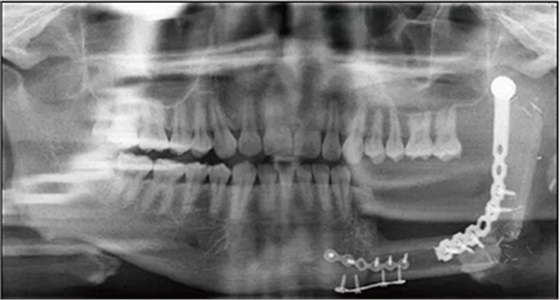

2014年6月9日于本院行下頜骨左側(cè)成釉細(xì)胞瘤切除術(shù)+下頜骨節(jié)段性切除術(shù)+重建板重建術(shù)+血管化腓骨肌皮瓣轉(zhuǎn)移修復(fù)術(shù)+鈦板內(nèi)固定術(shù)+血管吻合術(shù)+牽引釘植入術(shù)+拔牙術(shù)(圖2)。

2016年3月22日復(fù)查,全景片示34~37牙缺失,左下頜單層腓骨移植,腓骨與下頜骨對(duì)接處骨愈合良好,鈦板鈦釘在位(圖3)。